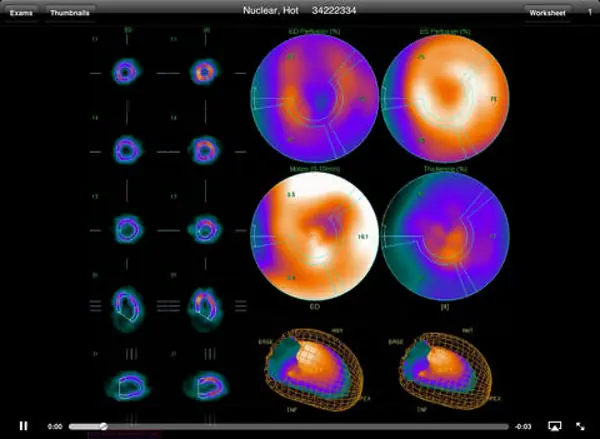

The software excels in medical imaging, supporting a wide range of modalities, including echocardiograms, vascular studies, and general ultrasound. UltraLinq allows healthcare providers to view, annotate, and analyze images directly within the platform, facilitating precise diagnoses and informed treatment plans. The platform’s customizable reporting tools further streamline clinical workflows, enabling the creation of detailed, specialty-specific reports tailored to the unique needs of each practice.